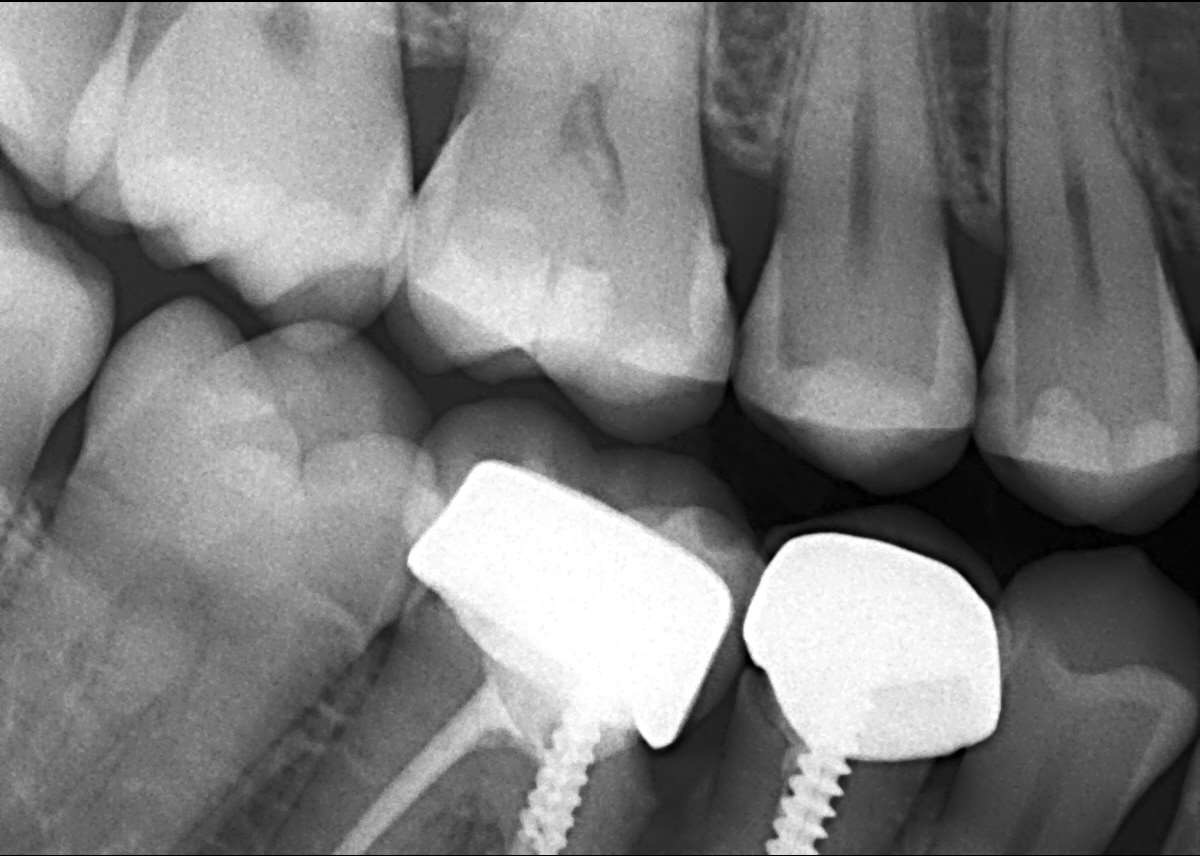

أعاني من الم في تلبيسة الاسنان ( سنين) مع نزيف دم عند استخدام خيط الاسنان

IMG_6199 IMG_6200

محتمل تم تلبيس الاسنان واللثه ملتهبه 0 2026-03-05T17:36:14+00:00 2026-03-05T17:36:14+00:00